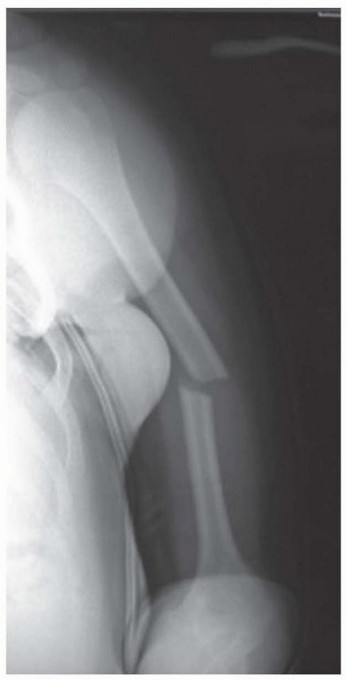

POSTERIOR GLENOHUMERAL DISLOCATION Incidence These injuries represent 2% to 4% of shoulder dislocations and 2…